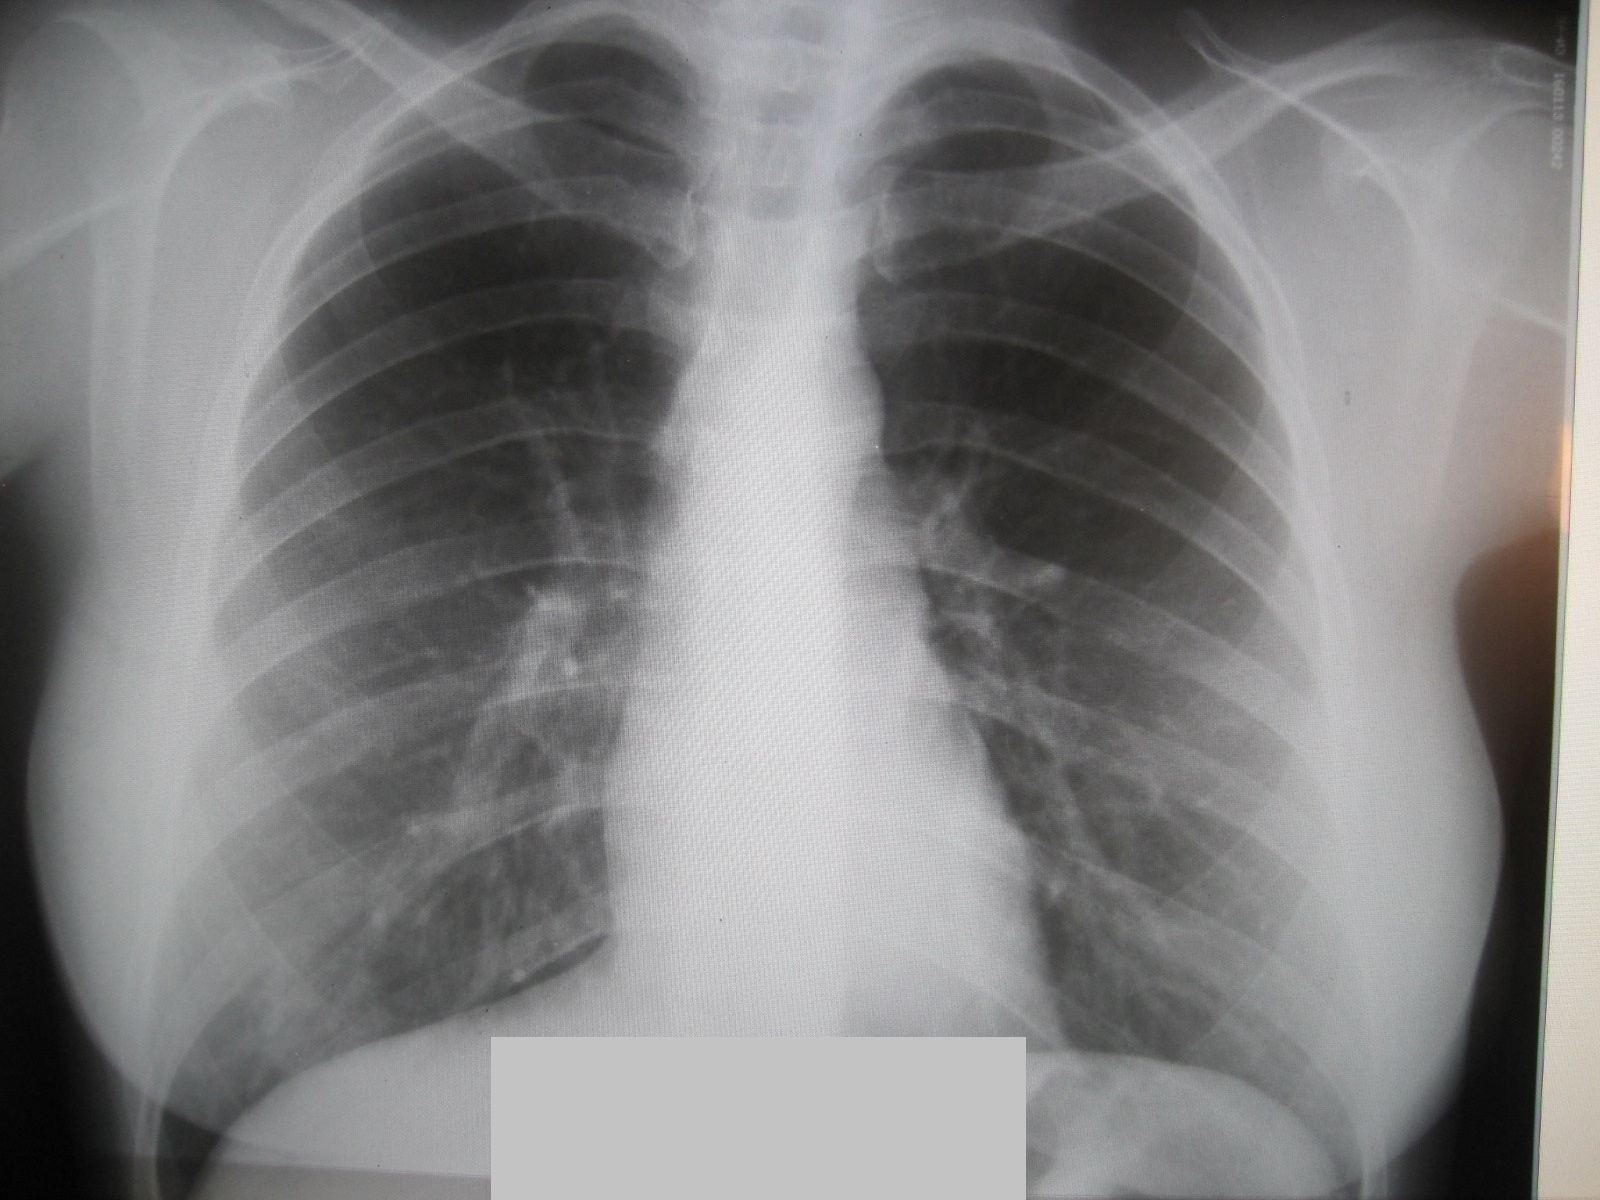

Снимок легких при туберкулезе является важным методом диагностики этого заболевания. На рентгеновских снимках можно увидеть изменения в легких, которые свойственны туберкулезу.

Диссеминированный туберкулез на рентгенограмме

Диссеминированный туберкулез рентген

Диссеминированный туберкулёз лёгких рентген

Диссеминированный туберкулез

Фотографии снимков легких при туберкулезе

В данной статье представлены многочисленные фотографии снимков легких при туберкулезе, чтобы помочь вам понять, как выглядят изменения легких на рентгеновских снимках при этом заболевании.